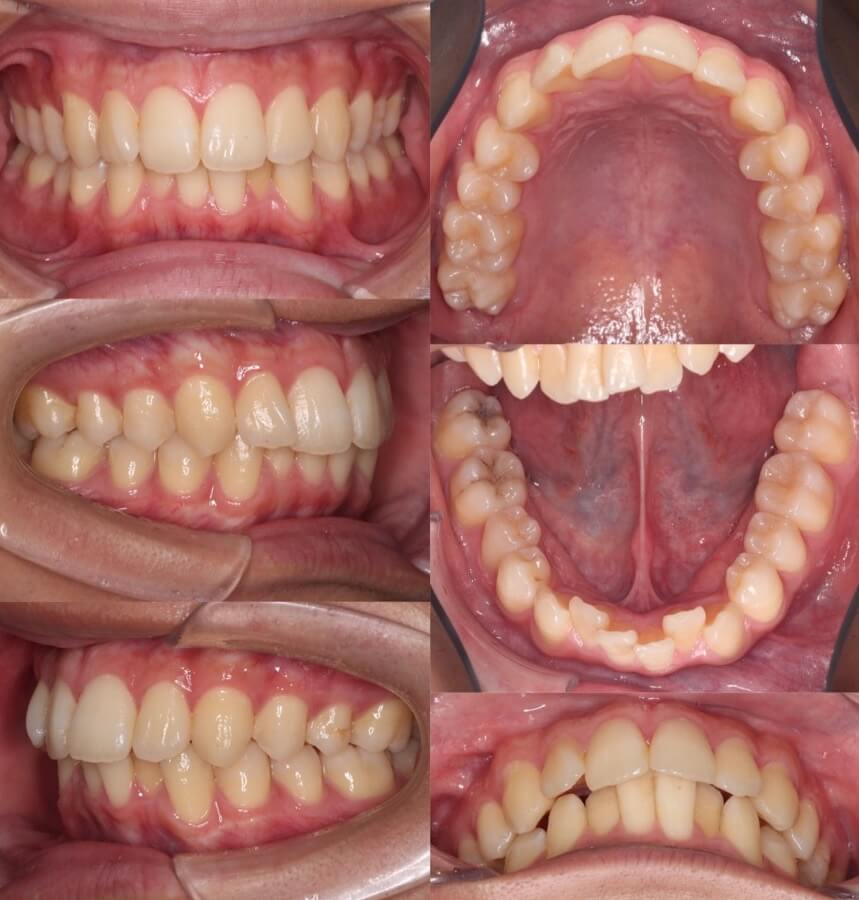

20代女性・軽度叢生・マウスピース型装置

下顎の非対称がある中で、正中線を合わせながらねじれている前歯を整えました。顎間ゴムをしっかりと使用したことが成功の鍵です。

<症例概要> 難易度★★★☆☆

主訴:前歯の突出

年齢・性別:20代女性

住まい:千葉県印西市

症状:叢生・正中線の不一致

治療方針:右下後方移動・左上後方移動・拡大・ストリッピング

治療装置:マウスピース型矯正装置(アライナー装置)

治療期間:1年11か月

アライナー枚数:40+32ステージ

リテーナー:上下フィックスタイプ+クリアタイプ

治療費用:990,000(税込)

代表的副作用:痛み・治療後の後戻り・歯根吸収・歯髄壊死・歯肉退縮

右下と左上と対角の歯並びを後方移動させながら拡大し、前歯を後方移動させながら正中線を一致させました。